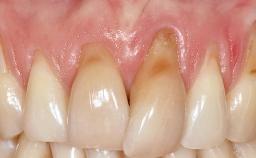

A 30-year-old woman was referred by her general dentist for evaluation of an esthetic complication related to previous implant treatment for congenitally missing maxillary lateral incisors. The patient’s chief complaint was the inadequate esthetic appearance of her smile. The case demonstrates the use of a combined approach to achieve optimal results. Two different flap designs - a tunnel technique and a coronally advanced flap - are employed based on the surgical objectives for the affected site.

Soft Tissue Anatomy Intact Defective